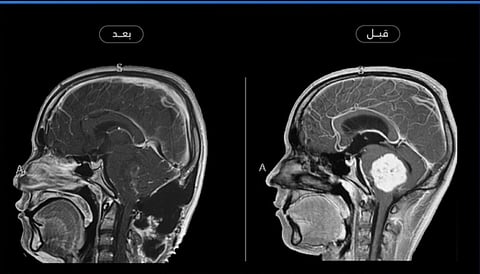

نجح فريق طبي في مستشفى الملك سلمان التخصصي، أحد مكونات تجمع حائل الصحي، في إجراء عملية دقيقة لاستئصال ورم نادر في الزاوية العَسرية المخيخية اليمنى لشاب في العشرين من عمره، كان يعاني من فقدان التوازن والسمع، واستفراغ متكرر، إضافة إلى صداع شديد ناتج عن ارتفاع الضغط داخل الجمجمة.

وأوضح الفريق الطبي أن العملية نُفذت على مرحلتين؛ الأولى تمثلت في تصريف السائل الدماغي الشوكي لتقليل الضغط داخل الجمجمة، فيما خُصصت المرحلة الثانية لاستئصال الورم باستخدام تقنيات جراحية دقيقة، نظراً لالتصاقه الشديد بالأعصاب والشرايين المحيطة بالمخيخ وجذع الدماغ، مما يزيد من احتمالية المضاعفات العصبية.

من جانبها، أوضحت الدكتورة عفراء السحيمي، قائدة مسار جراحة المخ والأعصاب بتجمع حائل الصحي، في حديثها لقناة "الإخبارية"، أن العملية استغرقت أكثر من 10 ساعات متواصلة، وتكللت بالنجاح التام دون أي مضاعفات تُذكر، مشيرةً إلى أن المريض قد تماثل للشفاء واستعاد قدرته على الاتزان، ويعيش حاليًا حياته اليومية بشكل طبيعي.